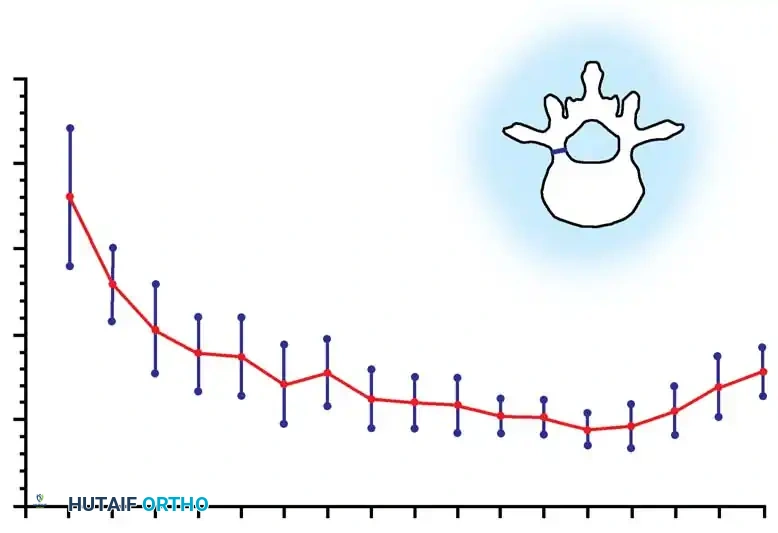

Biomechanics of Bone Grafting

Bone graft incorporates most effectively under compressive loads and is biologically disadvantaged in environments of distraction. Therefore, in scoliosis correction, if autogenous bone is limited, it should be preferentially concentrated on the concave side of the curve, which is subjected to compressive forces, rather than the convex side, which experiences tension. Furthermore, the farther the fusion mass is placed from the instantaneous axis of rotation, the more effectively it will neutralize movement across that axis.